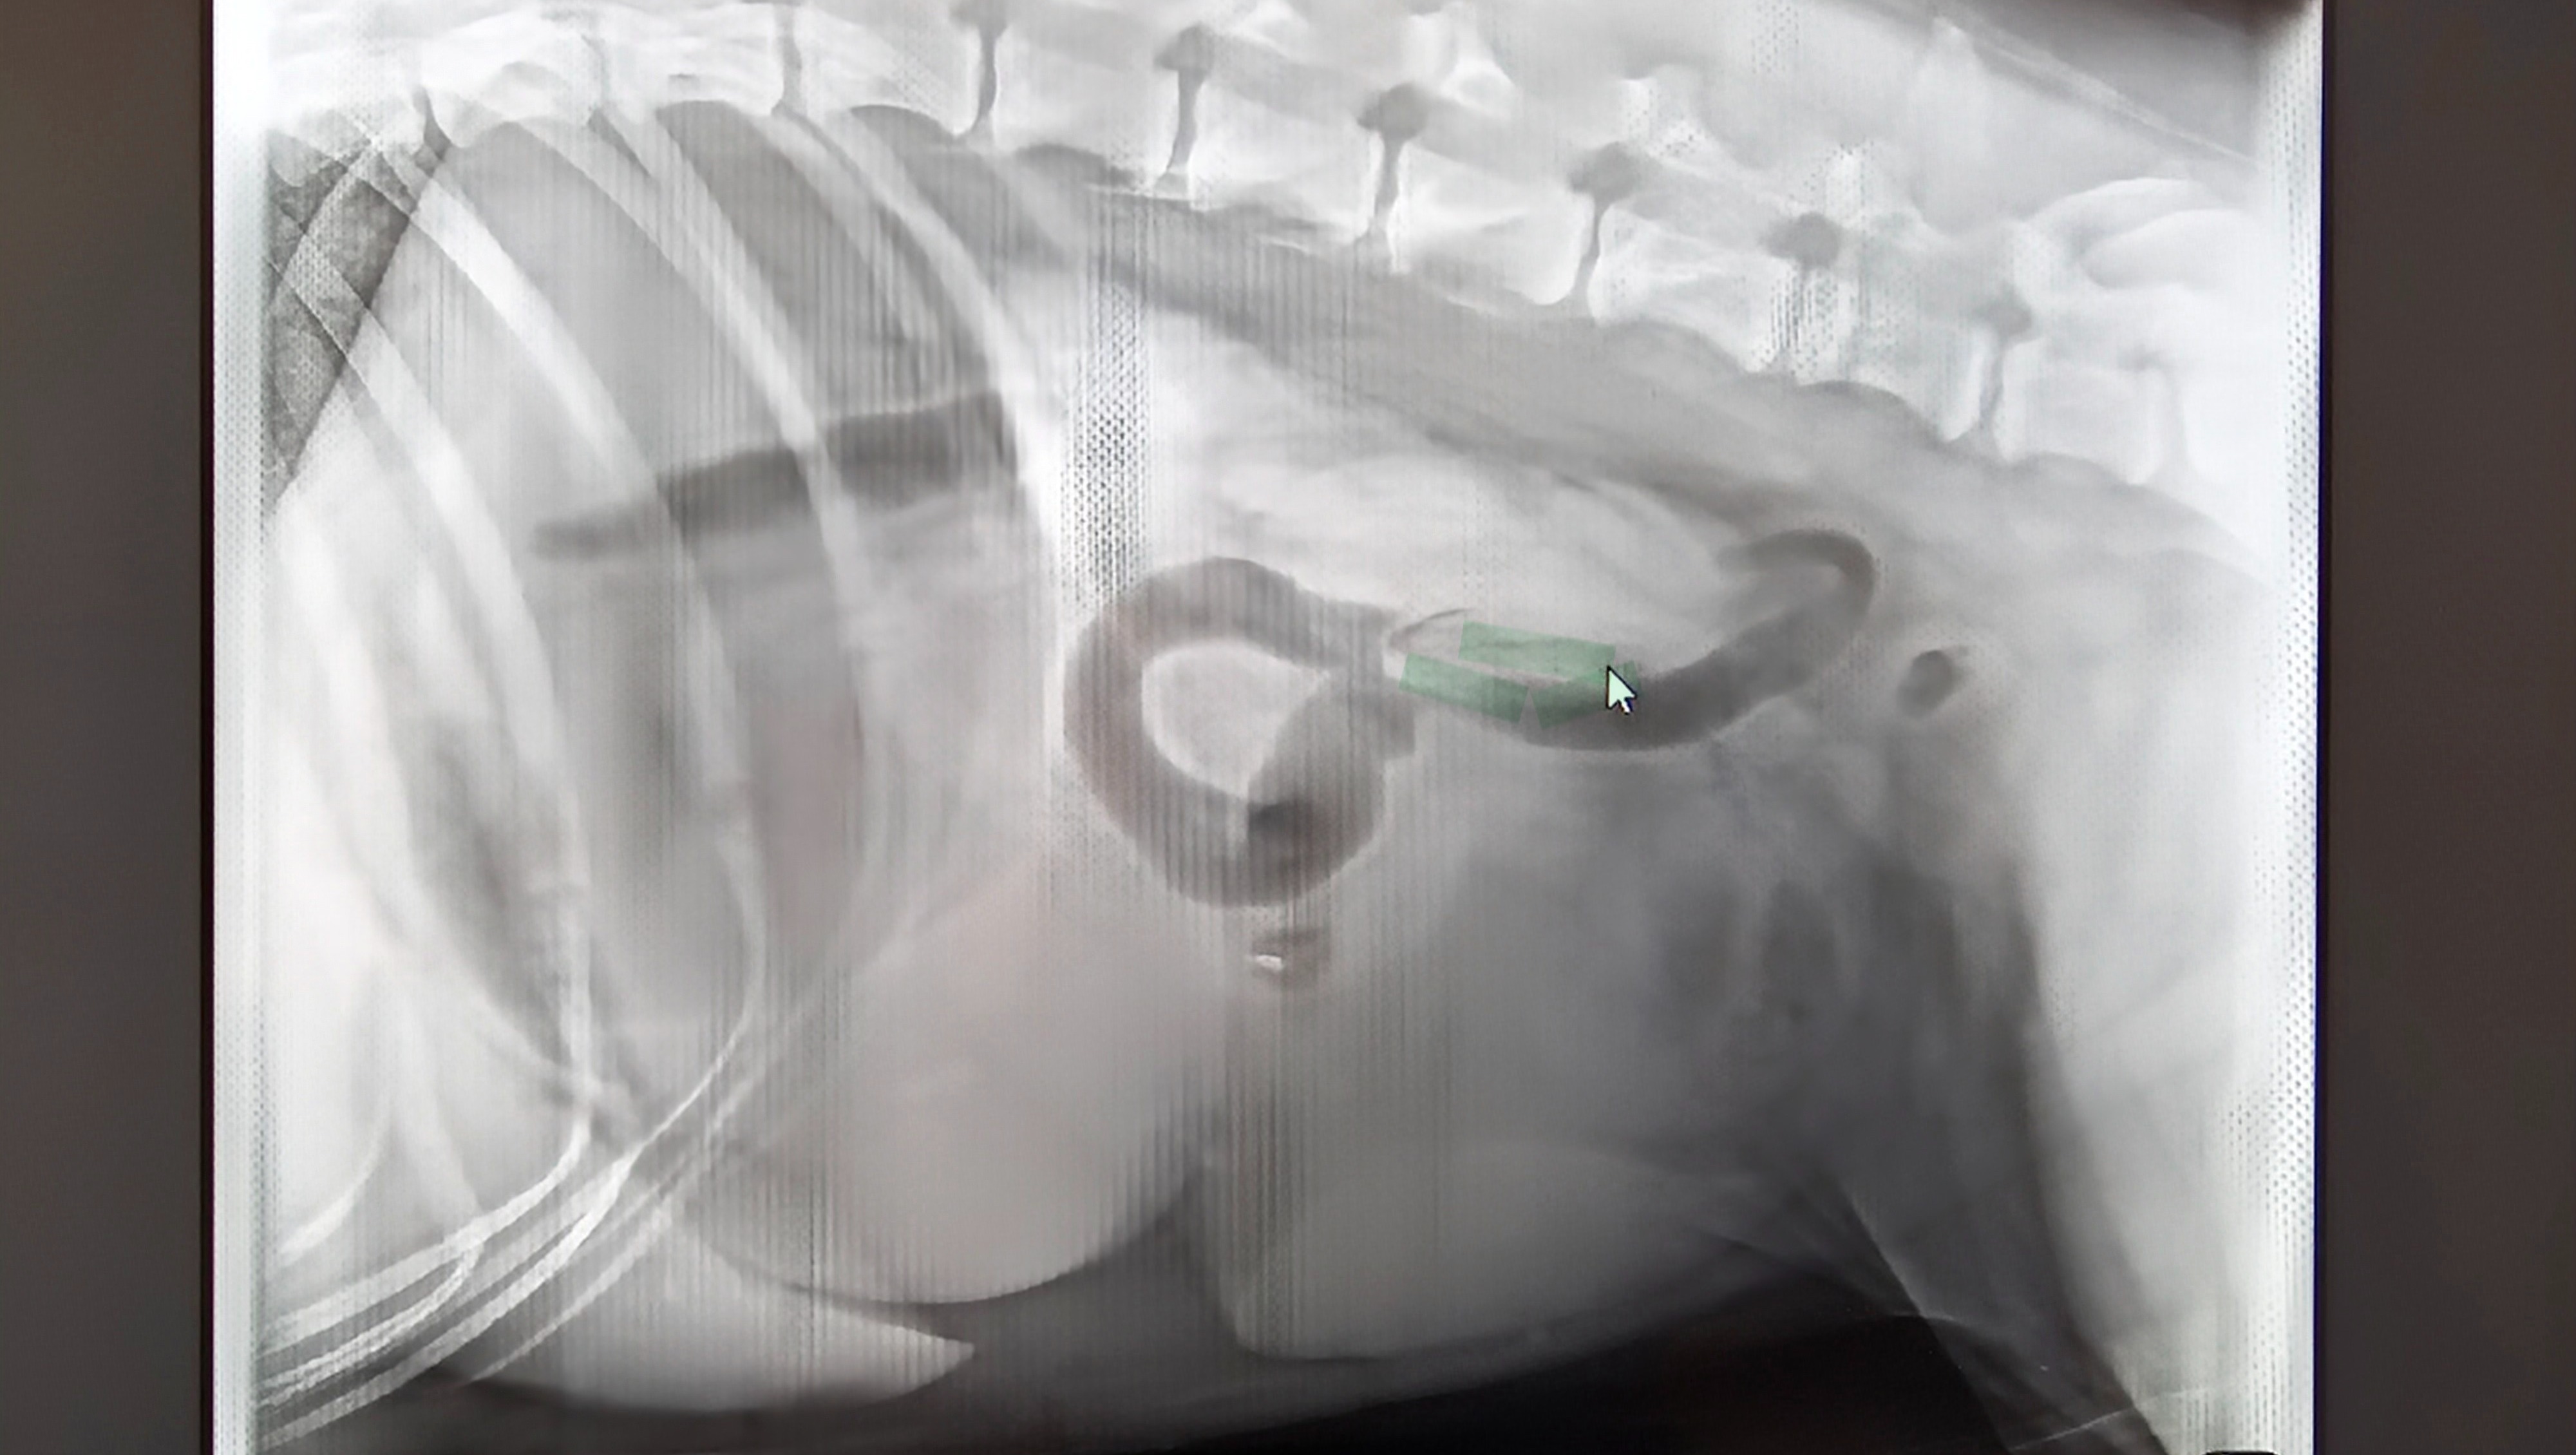

Hello, we are raising money to pay for the surgery for our dog Sebastian Hawk. He has an obstruction in his bowel that he has been unable to pass. The surgery costs start at between 6-9k.

Sebastian has been through so much in his 3 years of life, and he still has so much life to live. I have created this on behalf of my mom, Lucy MacKeige. We thank you for any help that you can give.